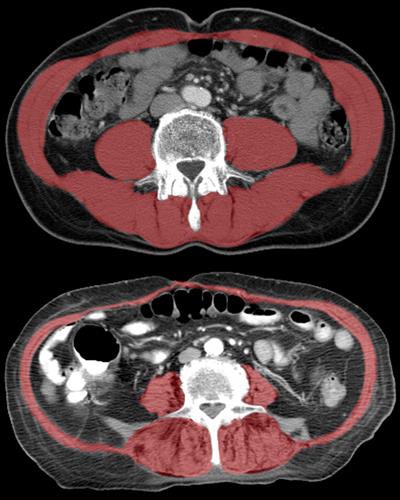

Researchers from the University of California, Davis and Wake Forest School of Medicine studied elderly patients with hip fractures who underwent CT scans. They found that reduced size and density of the so-called core muscle that stabilizes the spine were associated with frailty and reduced lifespan.

Along with fracture assessment, the CT scans were evaluated for additional measurements of the size and density of lumbar and thoracic muscle alongside the spine. Two experienced readers independently made the measurements while blinded to clinical data. The information was compared with mortality data from the National Death Index.